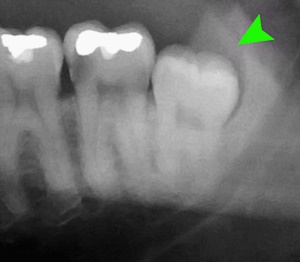

우리가 사랑니라고 부르는 것은 큰 어금니 중 세 번째 위치에서 제일 마지막에 나오는 치아입니다. 사랑니가 나올 때에는 첫사랑을 하듯이 아프다고 하여 붙여진 이름이라고 하는데요. 다른 이름으로는 ‘지치’라고 합니다. 지치는 사리를 분별할 수 있는 지혜가 생긴다는 뜻입니다.

사랑니는 보통 큰 어금니와 비슷하게 생겼습니다. 사랑니의 형태나 크기는 매우 다양하다고 하는데요. 보통의 어금니 보다 깊이 나기 때문에 빼기 어렵거나 절개를 통해 힘들게 빼야 하는 경우가 많습니다. 원래 사랑니는 음식물을 갈아 내기 위한 용도라고 하는데요. 이것은 치아의 퇴화 현상이라고 생각하시는 분들도 많이 계십니다.